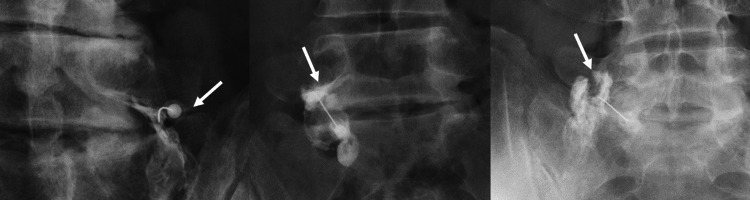

Three fluoroscopic contrast patterns during L5 selective nerve root block: Type 1 (contrast along nerve root), Type 2 (contrast in foramen but not around root), Type 3 (no root or foramen contrast). Pattern type affects diagnostic reliability.

4. Contrast injection first: Inject 0.1-0.3 mL of contrast to confirm position and observe the spread pattern — critical to verify limited, localized spread

• Inject 0.2-0.3 mL of contrast first to verify limited spread to the target nerve only

• Beware of lateral flow to the plexus, which would invalidate selectivity

• Evaluate contrast flow carefully — spread beyond the targeted spinal nerve either centrally into the foramen or laterally to the plexus increases the false-positive likelihood